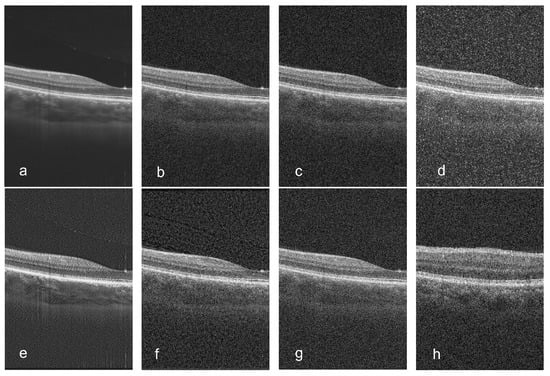

3.2. Comparison of Synthesized Noise with Other Noise Synthesis Models

3.3. Comparison of Denoising Results with Other OCT Denoising Methods